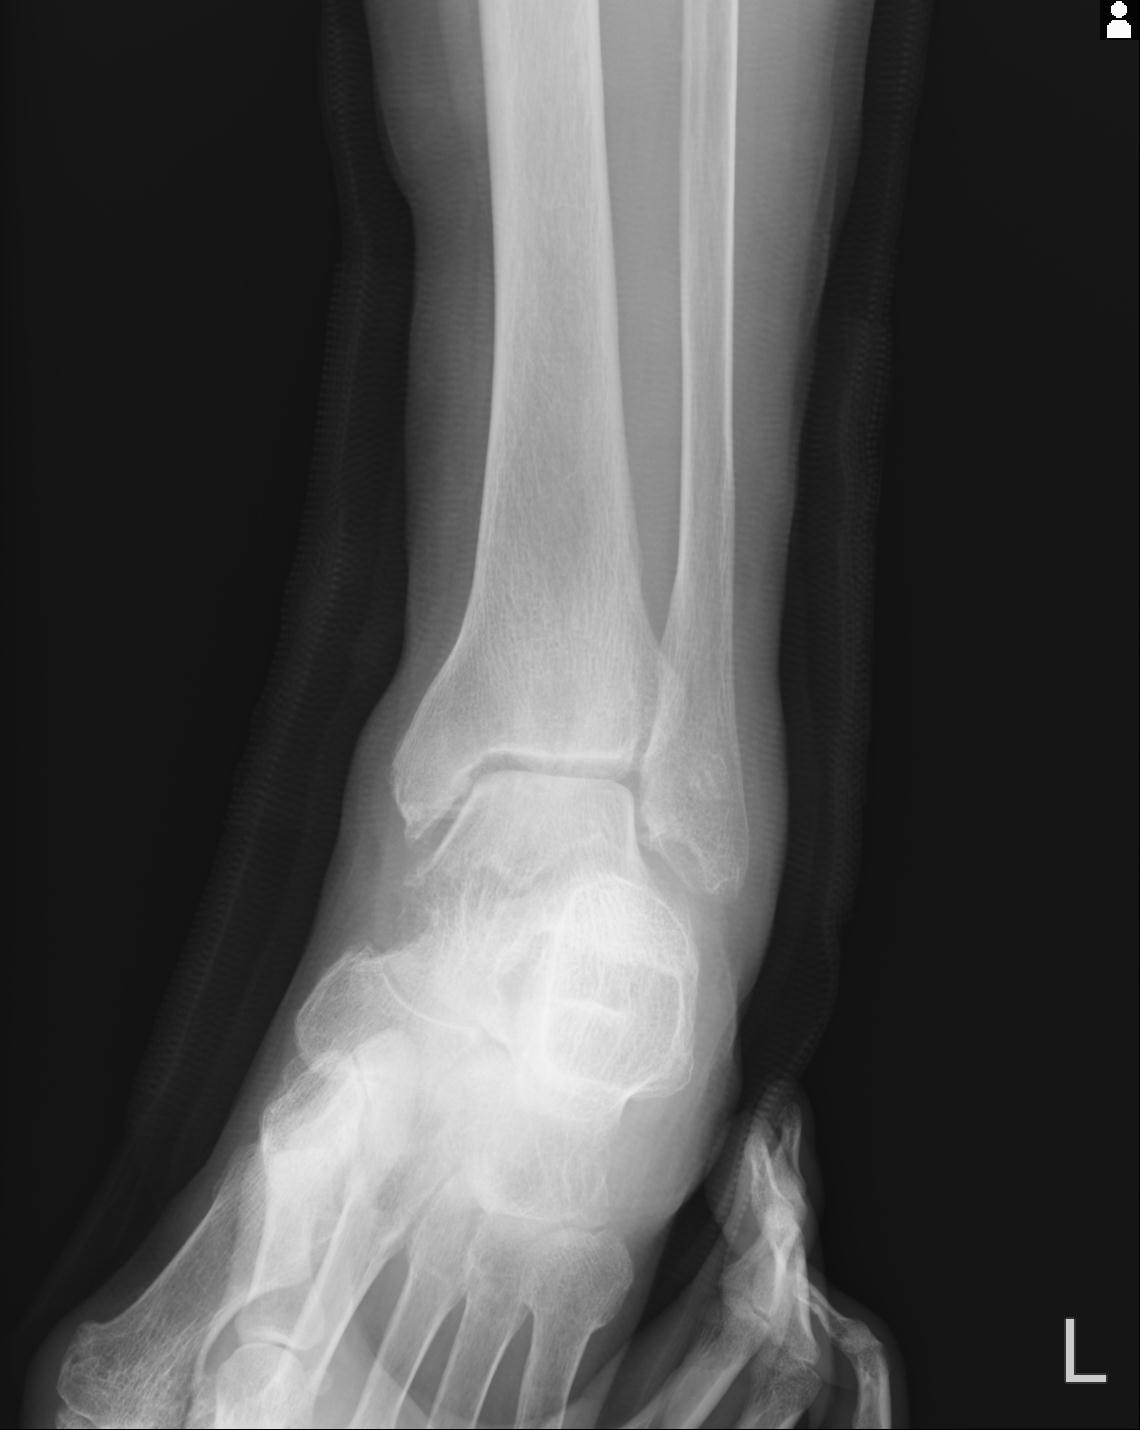

56476 8/28 4R 1/21 2R 左足関節 デジカメ写真 72歳女性 右足関節AS